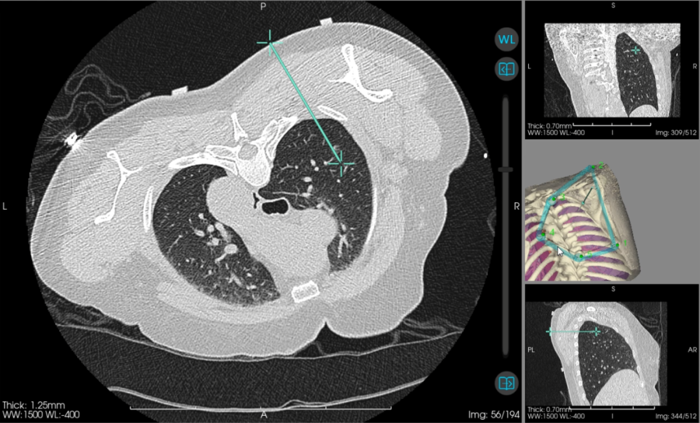

当天,心胸外科主任阳诺带领消融团队开展手术。他介绍,在术前,穿刺手术机器人系统基于患者CT影像,能自动构建详细的肺部3D立体模型,清晰呈现结节与周围血管、气管等重要组织的位置关系。

“它就像一位‘智能导航员”,精准规划穿刺路径、角度与深度,有效避开血管、气管等重要组织结构,将误差控制在毫米级。”阳诺说。

术中,机器人就像有了“智慧眼睛”和“稳定双手”,整个过程机械臂平稳导航,无需调针,实现对靶病灶的“一针到位”,减少了CT扫描次数和患者的辐射暴露。机器人的应用避免了人为因素可能带来的穿刺偏差,从而大大减少了对周围正常组织的损伤,显著降低了气胸、出血等并发症的发生率,也显著缩短了手术时间。

▲机器人引导下实际穿刺路径